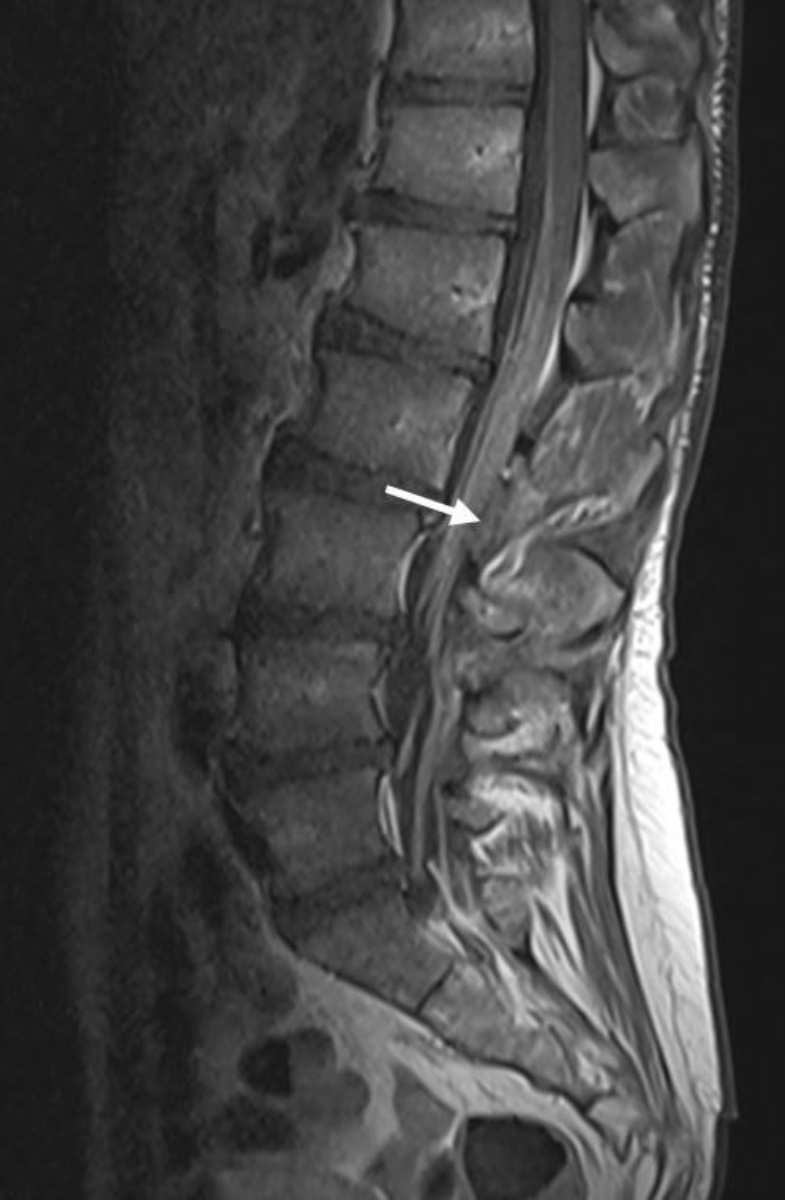

The second dose of ANV419 was given as planned and at the same dose two weeks after tumour-infiltrating lymphocyte transfer. Subsequently, the patient reported an increasing worsening of the previously present sensory polyneuropathy of the hands and feet, as well as new distal muscle weakness. Muscle weakening was measurable as a new distal paresis of both feet: foot elevation: 3/5, foot drop: 4/5, big toe elevation: 3/5, toe elevation: 3/5, according to the Medical Research Council (MRC) Scale (Grade 5: normal, Grade 4: movement against gravity and resistance, Grade 3: movement against gravity over the full range, Grade 2: movement of the limb but not against gravity, Grade 1: visible contraction without movement of the limb, Grade 0: no visible contraction). The patient developed an increasingly ataxic gait. Heel and toe gait was not possible. Both feet showed pall-hypoaesthesia, tested with 128 Hz-Diapason with result 4/8 (scale for assessment of disorders of vibratory sensitivity, range 0 to 8, with 8 being intact vibratory sensitivity). Furthermore, the muscle reflexes were absent bilaterally. A brain and spine MRI excluded the presence of central nervous system metastases but revealed a diffuse pathological contrast enhancement of the intraspinal nerves from cervical to sacrum including the cauda equina as well as a symmetrical pathological contrast enhancement of several cranial nerves on both sides. This finding was primarily compatible with the established diagnosis of chronic inflammatory demyelinating polyneuropathy (figures 2 and 3).

Figure 2Spine MRI (T1 TSE with gadolinium): smooth, non-nodular and diffuse pathological contrast enhancement of the intraspinal nerves and the entire cauda equina primarily compatible with the diagnosis of chronic inflammatory demyelinating polyneuropathy (CIDP).